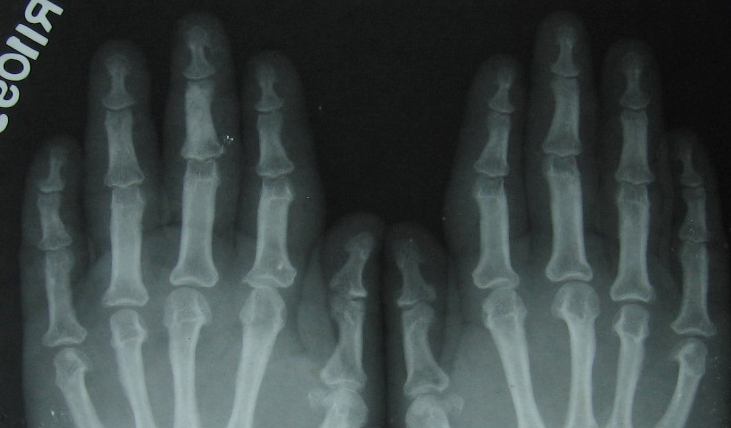

Fig.7 Zoomed view of 6